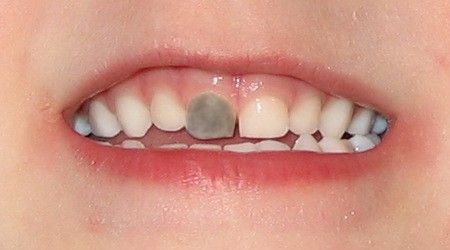

Identifying A Bruised Tooth

Most people don’t think of teeth when they think of bruises. Usually, it’s a black and blue knee versus a tooth. However, your teeth can become bruised, and it can be fairly painful. There are signs and symptoms you’ll need to be aware of, and you may need to visit the dentist depending on the severity. It may seem scary, but a bruised tooth is a common dental issue. And identifying a bruised tooth, is relatively straightforward.

CAUSES OF BRUISED TEETH

A bruised tooth is often caused by an injury to the tooth. Similar to a bruise on your skin, a bruised tooth is a reaction to excess pressure or force. While your tooth won’t turn black and blue like your skin, it can become discolored and turn a gray tint.

A bruised tooth is painful and may ache because the soft tissue and ligaments around your tooth essentially absorb the impact of the trauma or injury. Just like a bruise on your skin, the capillaries around the injured tooth burst. The capillaries then travel to the opening of the tip of the root, which gives the tooth a pinkish discoloration.

The pinkish discoloration may turn gray, which can be permanent. A gray tooth may mean that the pulp inside your tooth is impacted, resulting in a higher risk of infection or decay. This can result in the need for a root canal Brentwood. If your tooth does not turn from pink to gray, you may be in the clear. However, you should see the best dentist Brentwood has, as they will want to monitor your tooth and help you in identifying a bruised tooth.